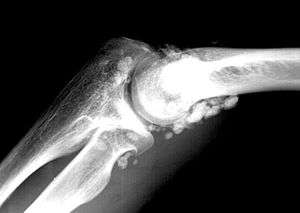

| X-ray of an elbow affected by synovial chondromatosis | |

Synovial chondromatosis (synonyms include synovial osteochondromatosis, primary synovial osteochondromatosis, and synovial chondrometaplasia) is a disease affecting the synovium, a thin flexible membrane around a joint. It is also known as Reichel's syndrome or Reichel-Jones-Henderson syndrome, named after Friedrich Paul Reichel, Hugh Toland Jones and Melvin Starkey Henderson.[1]

In the disease, the thin flexible membrane of the synovium gradually forms blisters which calcify and enlarge. These nodules eventually break free and float around the joint space becoming larger – these add to the discomfort and stiffness of the joint.

The disease generally affects only one of the larger weight bearing joints (hip, ankle, knee) – although the elbow, and wrist can also be affected. Rarely involves the temporal mandibular joint.[3]